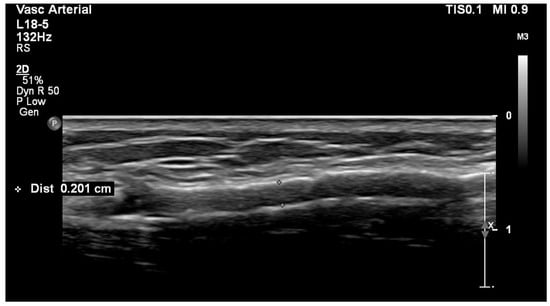

5. Significant Stenosis Definition by Ultrasonography